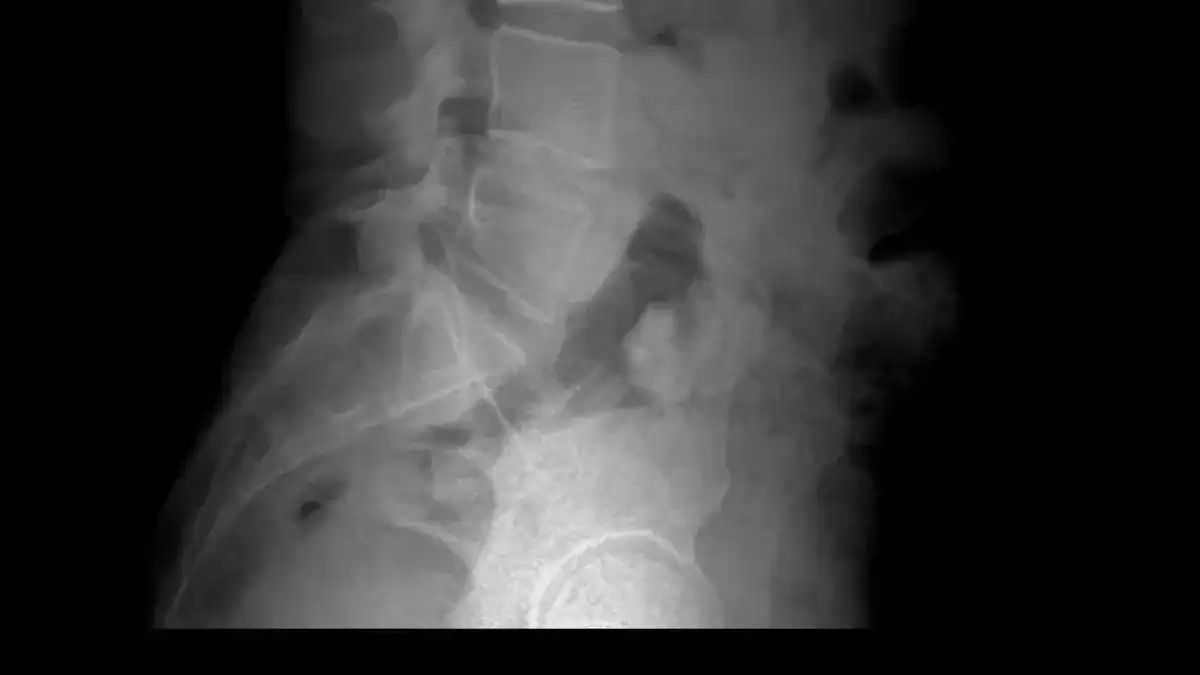

• X-ray: Doctors use X-rays to check for bone abnormalities. They can rule out fractures or other bone-related issues.

• X-ray: While X-rays only show bones, they help check for bone-related issues like vertebral fractures.